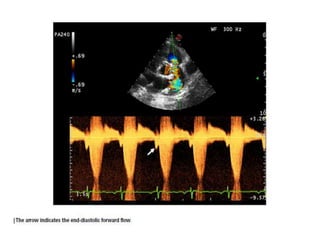

PR

• PR, occurring as a result of transannular patching, pulmonary

valvotomy or valvectomy, or any other procedure that disrupts

the valve, is an important factor in the long-term outcomes of

patients with repaired TOF.

• It is a key initiating element in a pathophysiologic cascade that

leads to RV dilatation and dysfunction, which in turn has been

linked to secondary TR, decreased exercise capacity, and

increased risk for atrial and ventricular arrhythmias, as well as

sudden cardiac death.

• Therefore, evaluation of PR is an essential component of the

echocardiographic examination in these patients.

• PR jets are easily visualized by color Doppler in the RVOT,

especially when evaluated in the parasternal long-axis and

short-axis planes.

• PR jet(s) may be overlooked by color Doppler because the

flow is laminar with low velocity.

• Predictors of severe PR by Doppler included diastolic flow

reversal in the main or branch PAs coupled with a PR jet width

on color Doppler > 50% of the pulmonary annulus .

• Others parameters ; PR jet width/pulmonary annulus ratio

cutoff of >0.7 to identify a CMR PR fraction > 40%.

• Short deceleration time in the PR spectral Doppler signal is

usually indicative of severe PR and often leaves a long period

of ‘‘no flow’’ or ante grade flow in the latter part of diastole.

• This spectral appearance relates to the rapid equilibration of

PA and RV diastolic pressures.

• The duration of the PR signal in the spectral Doppler trace

compared with the total duration of diastole has been called

the PR index

• A value < 0.77 has been shown to have high sensitivity and

specificity for identifying patients with CMR-derived PR

fractions > 25%, which can be viewed as ‘‘significant.’’

• A pressure half-time < 100 msec has good sensitivity and

specificity for severe PR.

• It should be noted that this measurement might not be

reliable in the presence of high RV end-diastolic pressure,

which contributes to early pressure equilibration between the

MPA and the right ventricle.

Evaluation of PR by Doppler echocardiography showing mild, moderate, and severe degrees.

(Top row) Spectral Doppler tracing. Mild regurgitation is characterized by a persistent flow

gradient at end-diastole and moderate regurgitation by equilibration of pressures between

the MPA and right ventricle only at end-diastole, and severe regurgitation is associated with

early diastolic pressure equilibration. (Bottom row) Pulse Doppler interrogation in the LPA

showing degrees of diastolic flow reversal.